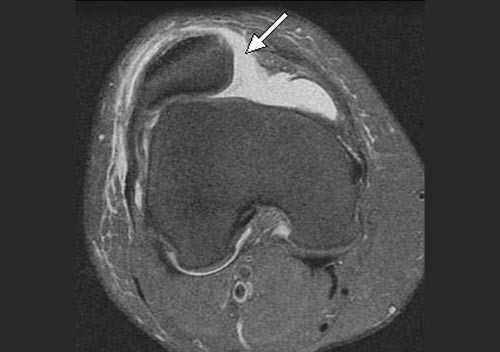

В большинстве случаев врач-травматолог легко диагностирует привычный вывих надколенника. Для этого проводится серия нагрузочных тестов, во время которых пациент демонстрирует страх получения повторного вывиха. Окончательный диагноз ставится после проведения магнитно-резонансной томографии (МРТ) коленного сустава. Как правило, исследование обнаруживает признаки повреждения медиальной пателло-феморальной связки, состояние подвывиха надколенника и признаки травматических повреждений хрящевого покрова.